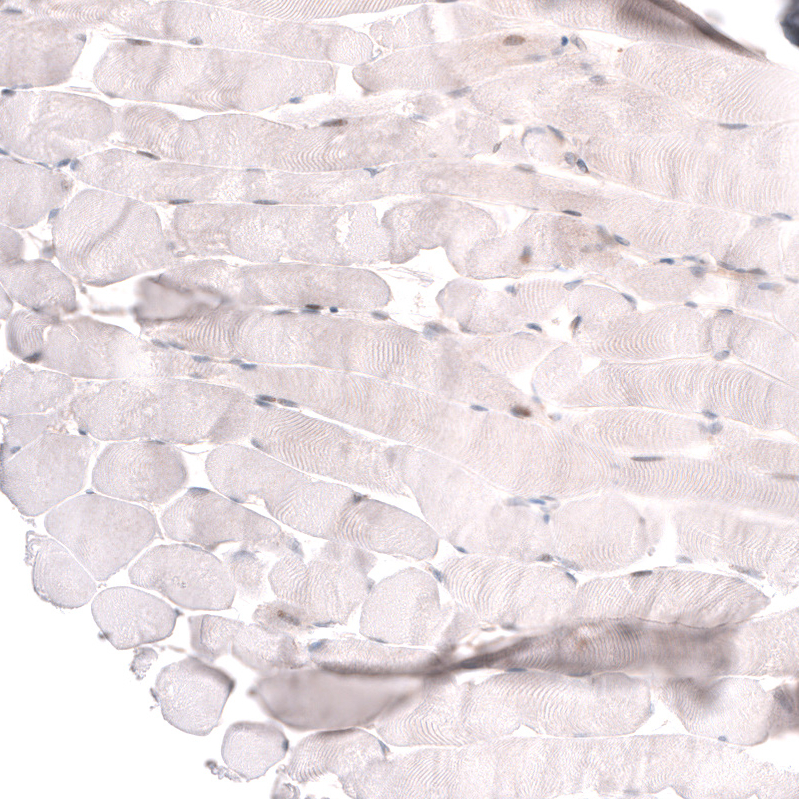

Immunohistochemistry analysis in human prostate and skeletal muscle tissues using AMAb91898 antibody. Corresponding ADAM10 RNA-seq data are presented for the same tissues.